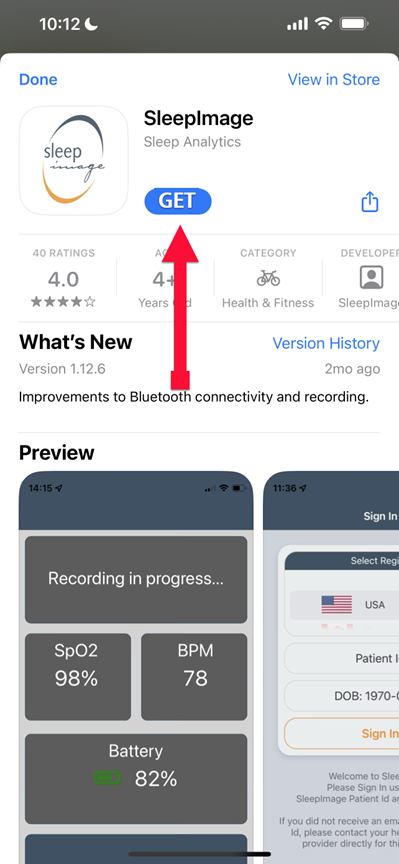

SLEEPIMAGE APP (iPhone)

SLEEPIMAGE APP (iPhone)

SLEEPIMAGE APP (iPhone)

SLEEPIMAGE APP (iPhone)

SLEEPIMAGE APP (iPhone)

SLEEPIMAGE APP (iPhone)

SLEEPIMAGE APP (iPhone)

SLEEPIMAGE APP (iPhone)

SLEEPIMAGE APP (iPhone)

SLEEPIMAGE APP (iPhone)

SLEEPIMAGE APP (iPhone)

SLEEPIMAGE APP (iPhone)

SLEEPIMAGE APP (iPhone)

SLEEPIMAGE APP (iPhone)

SLEEPIMAGE APP (iPhone)

SLEEPIMAGE APP (iPhone)

SLEEPIMAGE APP (iPhone)

SLEEPIMAGE APP (iPhone)

SLEEPIMAGE APP (iPhone)

SLEEPIMAGE APP (iPhone)

SLEEPIMAGE APP (iPhone)

SLEEPIMAGE APP (iPhone)

SLEEPIMAGE APP (iPhone)

SLEEPIMAGE APP (iPhone)

SLEEPIMAGE APP (iPhone)

SLEEPIMAGE APP (iPhone)